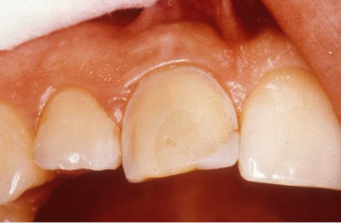

These are full crowns. Before shows old failing amalgam restorations.